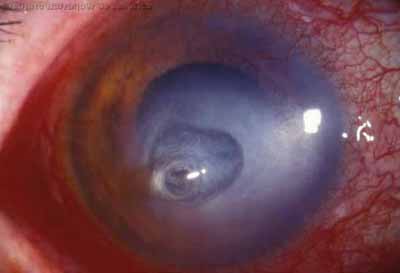

En su evolución se observará aumento del edema, aparición de un anillo inmunológico (Wessely), agrandamiento y coalescencia de los infiltrados que progresan hacia la formación de un absceso, queratolisis superficial, adelgazamiento y perforación corneal.

Anillo inmunológico de Wessely

PAS

• Es la expresión de la interacción de los antígenos extraños con los anticuerpos que se difunden desde los vasos limbares hacia el estroma.

• Representa la formación de un complejo inmune que activa el sistema del complemento.

• El anillo de Wessely contiene principalmente neutrófilos

• Puede aparecer en procesos no infecciosos